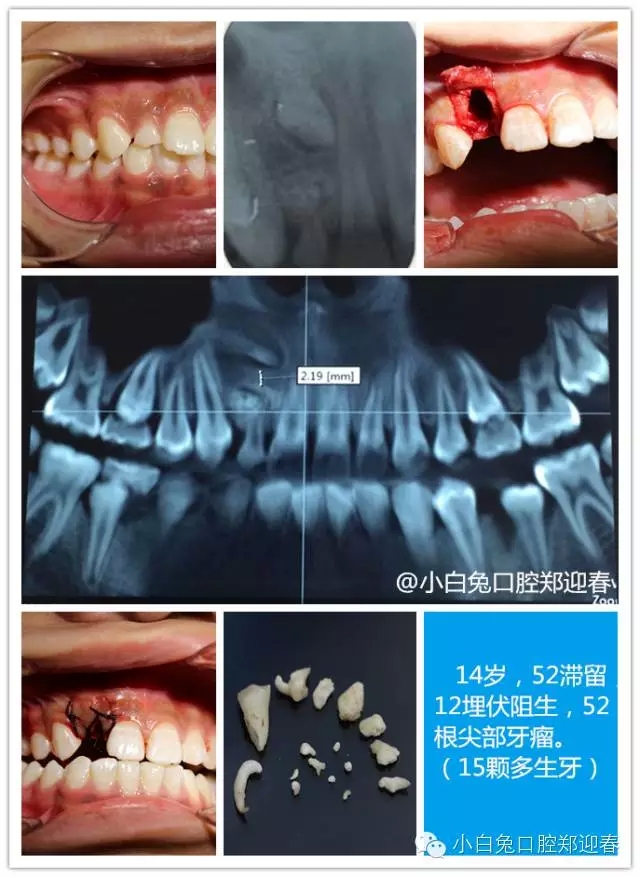

“多生牙”案例集錦(鄭穎春)......

額外牙可發(fā)生于乳牙列,也可發(fā)生于恒牙列,但恒牙列發(fā)生率多于乳牙列。額外牙經(jīng)常在上頜出現(xiàn),上、下頜出現(xiàn)比例為10∶1,可單個(gè)或多個(gè)、單側(cè)或雙側(cè)出現(xiàn),形態(tài)可同正常牙,也可是畸形牙、過(guò)小牙。